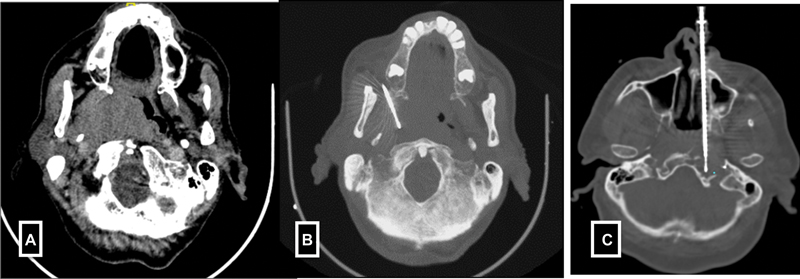

F)Head and neck lesions-Deep seated head and neck biopsies are most commonly performed under CT guidance. Various approaches such as subzygomatic, retromandibular, paramaxillary and submastoid, transoral and posterior approaches are commonly used.[9] In contrast, the biopsies of superficial organs such as lymph node, submental, parotid glands, and thyroid gland lesions are done under USG guidance ([Fig. 4]).

| Figure 4:(A-B) Paramaxiiary approach for parapharyngeal mass biopsy. (C) Trans nasal approach for petrous mass biopsy.